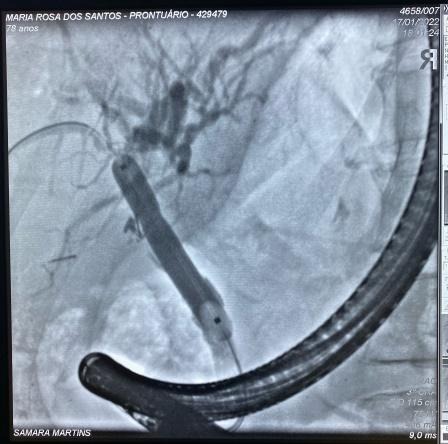

Paciente manteve assintomática e acompanhamento ambulatorial para programação de tratamento definitivo, que foi optado pela dilatação da via biliar (balão CRE 6-8mm) e inserção de prótese metálica auto-expansível totalmente recoberta (10 x 80mm) (Fig 5). O procedimento foi realizado 90 dias após a primeira CPRE sem intercorrências e optado pela retirada após 1 ano. A última CPRE foi realizada 12 meses após a inserção da prótese metálica no qual foi possível retirá-la, extrair o cálculo da via biliar proximal e obter uma colangiografia sem sinais obstrutivos ou extravazamentos ao final do procedimento (Fig 6).

Fig 6. Imagens colangiográficas da última CPRE: A. Imagem radiológica da prótese metálica inserida no procedimento anterior; B. Imagem colangiográfica de coledocolitiase em via biliar proximal; C. Colangiografia de oclusão final.